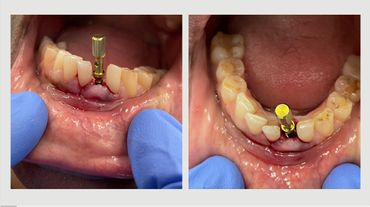

Single, Multiple Unit, and adjunct to Full Arch

Where and how to use 2.9 Narrow implant